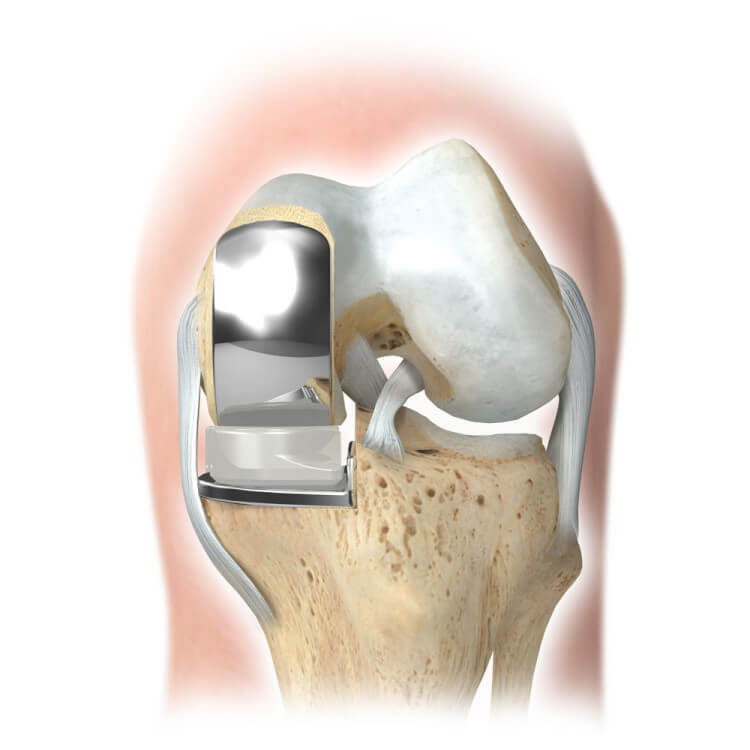

Фотографии и примеры протезирования коленного сустава